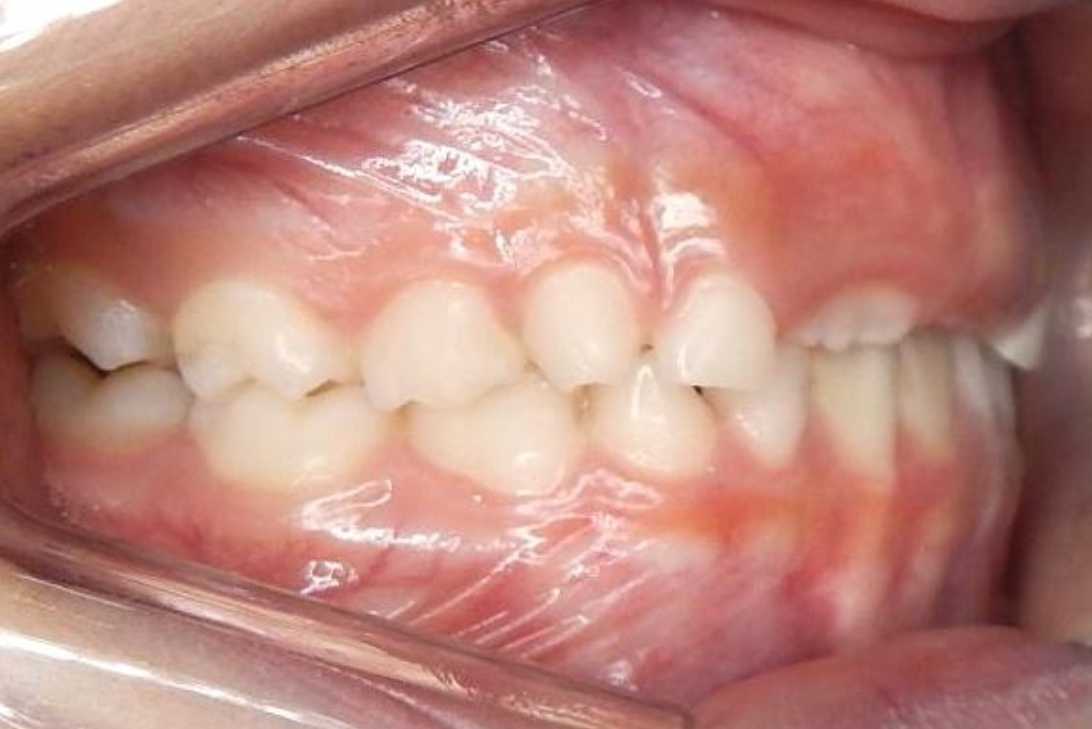

ORTODONTIA MIOFUNCIONAL

J.N.E.